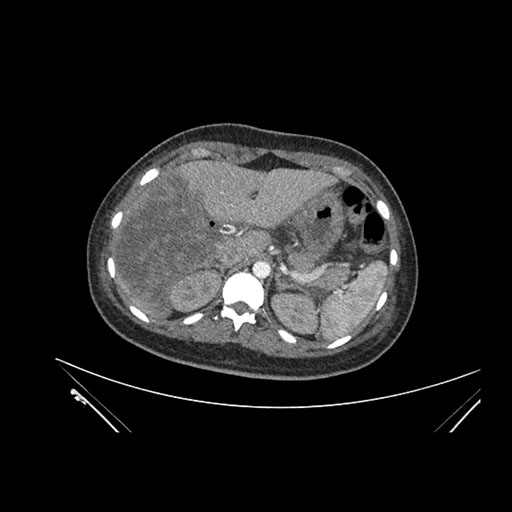

Axial Venous

Imaging analysis

Based on initial findings, which issue(s) would you be most concerned about?